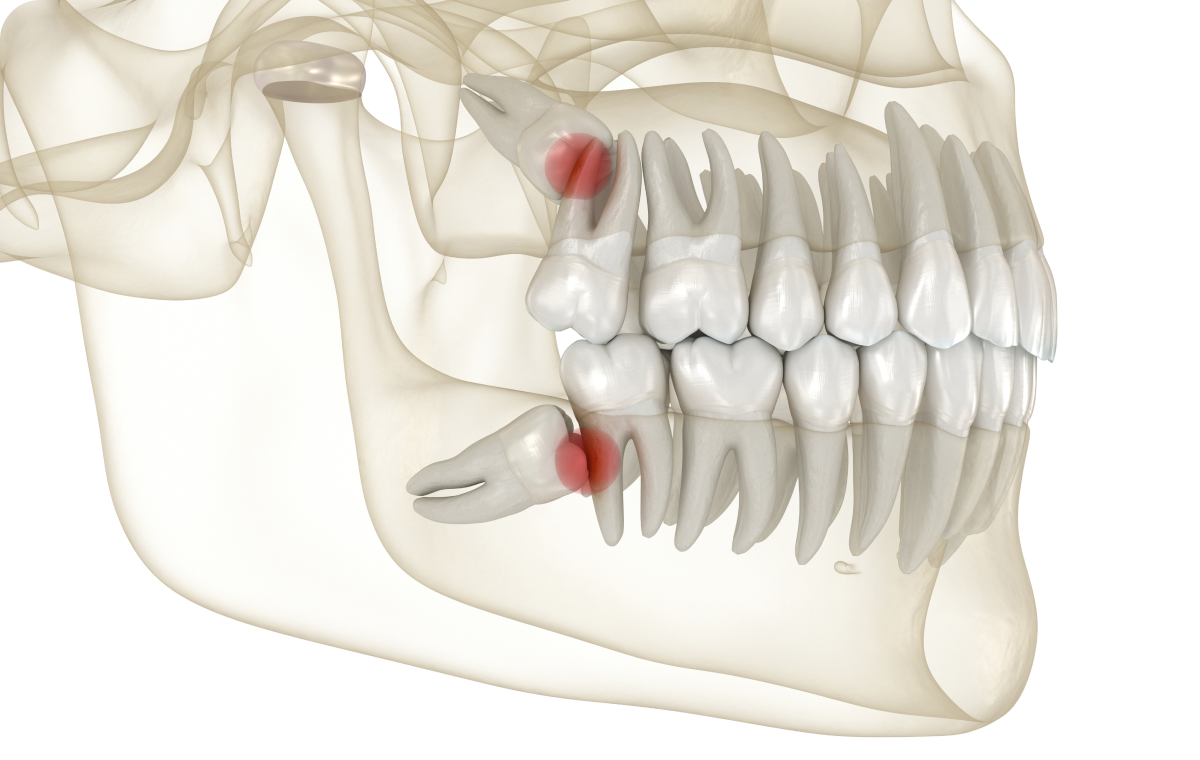

Dents de sagesse

Les dents de sagesse peuvent poser de nombreux problèmes de santé bucco-dentaire, notamment lorsqu’elles sont mal positionnées. Read More…